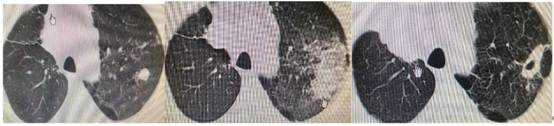

陈大爷的消融手术由微创治疗经验丰富的医师完成,利用高分辨CT做引导,做完穿刺活检后,将射频消融针尖精确瞄准到肿瘤中心,确保电极将肿瘤全面包住,对肿瘤组织充分加热,最终利用热产生的生物学效应直接导致肿瘤细胞发生不可逆损伤或凝固性坏死。半小时后,陈大爷已经回到了病房,他感叹道:一根针就悄无声息地把我的肿瘤治好了,而且我感觉现在就能下床活动了。术后第二天,陈大爷复查CT后出院了。病理结果证实为肺腺癌,术后3月复查CT:病灶已经逐渐吸收形成空洞了,就像在肺里留下了一道“烫伤疤痕”。更重要的是,热消融能保留更多健康肺组织。以陈大爷为例,若接受肺段切除将损失约200ml肺容积,而消融仅影响30ml区域,这对保持老年人呼吸功能至关重要。

图:治疗前(左)、射频消融后1天(中)和射频消融后2个月(右)。